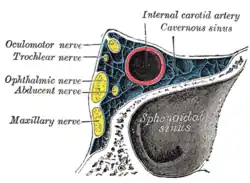

C4: Cavernous segment

The cavernous segment, or C4, of the internal carotid artery begins at the petrolingual ligament and extends to the proximal dural ring, which is formed by the medial and inferior periosteum of the anterior clinoid process. The cavernous segment is surrounded by the cavernous sinus.

In this part of its course, the artery is situated between the layers of the dura mater forming the cavernous sinus, but covered by the lining membrane of the sinus. It at first ascends toward the posterior clinoid process, then passes forward by the side of the body of the sphenoid bone, again curves upward on the medial side of the anterior clinoid process, and perforates the dura mater forming the roof of the sinus. The curve in the cavernous segment is called the carotid siphon. This portion of the artery is surrounded by filaments of the sympathetic trunk, and on its lateral side is the abducent nerve, or cranial nerve VI.